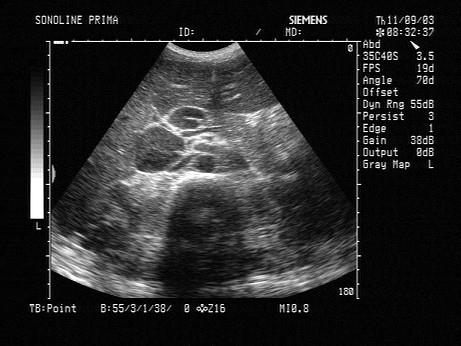

问题 患者,发热,颈部及腹股沟可触及包块。清洁灌肠后,行中腹部超声检查,声像图表现如图,最可能的诊断是?(?)

选项 A.淋巴瘤 B.胰头癌 C.结肠癌 D.腹腔结核 E.腹膜后肿瘤

答案 A